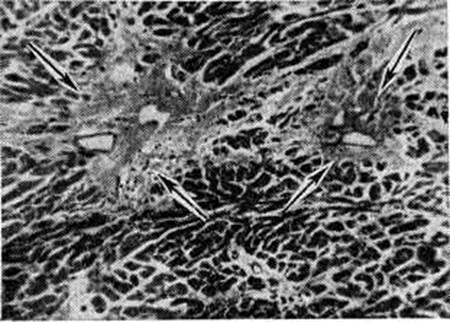

КардиосклерозКардиосклероз (греческий kardia сердце + sklerosis уплотнение; синонимы: миокардиосклероз, миофиброз, склероз сердца, фиброз сердца) — разрастание соединительной ткани в сердечной мышце, наступающее обычно вслед за гибелью мышечных волокон или параллельно ей. Кардиосклероз, как правило, процесс вторичный, является исходом различных по своей этиологии и патогенезу процессов в миокарде. Кардиосклероз может быть проявлением ишемической болезни сердца (смотри полный свод знаний). Первичный Кардиосклероз встречается крайне редко. Морфологически различают постинфарктный Кардиосклероз, заместительный Кардиосклероз, миокардитический Кардиосклероз и Кардиосклероз вследствие кардиомиопатий (смотри полный свод знаний) различной этиологии; Кардиосклероз развивается также при базедовой болезни. Постинфарктный кардиосклероз (крупноочаговый Кардиосклероз, мозоль миокарда, рассеянный очаговый Кардиосклероз, постинфарктный рубец) возникает вследствие нарушения коронарного кровообращения, приводящего к инфаркту миокарда (смотри полный свод знаний) как проявлению ишемической болезни сердца. Значительно реже постинфарктный Кардиосклероз является следствием некроза участка миокарда в результате эмболии венечных артерий тромботическими массами при эндокардите митрального клапана или пристеночных тромбах в левой половине сердца; поражения ветвей коронарных артерий при ревматизме или артериитах различной природы (например, при генерализованном неспецифическом артериите, или болезни Такаясу, нодозном панартериите), при сужении их устьев в результате сифилитического мезаортита, стенозе аортального отверстия при сифилитическом пороке сердца или при изолированном кальцинозе аортальных клапанов. По-видимому, следствием эмболии является также крупноочаговый Кардиосклероз, наблюдающийся избирательно в области верхушки сердца при кардиомегалиях, связанных с болезнью Шагаса, и при идиопатической гипертрофии сердца, сопровождающихся, как правило, образованием пристеночных тромбов в левом желудочке сердца. Формирование Кардиосклероз при крупноочаговом инфаркте миокарда происходит путём замещения погибшего участка мышцы сердца молодой соединительной тканью. Погибшие мышечные волокна подвергаются коагуляции и последующему распаду сначала с участием лейкоцитов, а затем макрофагов, поглощающих продукты распада. Одновременно происходит размножение фибробластов, новообразование капилляров, тонкостенных синусоидальных сосудов из сохранившихся участков стромы, особенно вокруг сосудов, накопление гликозаминогликанов и формирование молодой соединительной ткани с образованием сети аргирофильных и коллагеновых волокон. Количество коллагеновых волокон по мере созревания соединительной ткани увеличивается, они приобретают упорядоченное расположение параллельно друг другу, количество гликозаминогликанов и клеточных элементов уменьшается, часть сосудов запустевает и образуется плотный соединительнотканный рубец (цветной таблица, ст. 144, рисунок 1) с небольшим количеством клеточных элементов и сосудов, иногда в дальнейшем с отложением солей извести. Эластические волокна в рубце представлены то очень скудно в виде отдельных беспорядочно расположенных волоконец, то в большом количестве в виде густых сетей, расположенных между пучками коллагеновых волокон. Иногда в рубец, особенно по периферии или вокруг сохранившихся интрамуральных артерий, могут быть включены небольшие группы сохранившихся миокардиальных клеток, часто с различными проявлениями дистрофических изменений. В полях постинфарктного Кардиосклероз после обширных инфарктов в центре иногда в течение длительного времени сохраняются участки некротизированного миокарда. Заживление мелкоочаговых инфарктов миокарда протекает аналогичным образом, отличаясь лишь размерами образовавшегося рубца и скоростью его формирования. Постинфарктный Кардиосклероз соответственно размерам перенесённого инфаркта может захватывать всю толщу миокарда или отдельные его слои; после повторных инфарктов могут наблюдаться обширные рубцы разной локализации, протяжённости, изолированные или смыкающиеся друг с другом. Наиболее частой локализацией Кардиосклероз являются верхушка сердца, передняя, несколько реже задняя стенка левого желудочка, межжелудочковая перегородка, папиллярные мышцы. Постинфарктный Кардиосклероз правого желудочка в ряде случаев наблюдается одновременно с постинфарктным Кардиосклероз левого желудочка, обычно являясь продолжением изменений в левом желудочке. Изолированное поражение правого желудочка наблюдается очень редко. Постинфарктный Кардиосклероз предсердий обнаруживается, как правило, одновременно с рубцовыми изменениями в левом желудочке, но обычно не является их продолжением; изолированный постинфарктный Кардиосклероз предсердий встречается редко. |

Сердце при постинфарктном Кардиосклероз увеличено, полости его расширены; на разрезе в стенке видны белесоватые поля соединительной ткани различной протяжённости и формы. В зависимости от размеров инфаркта они могут иметь вид прослоек или распространяться на всю толщу миокарда — так называемый мозоль миокарда (цветной рисунок 4). В последнем случае стенка желудочка истончена, кожистого вида, иногда вследствие отложения солей извести хрустит при разрезе. В результате истончения стенки образуется так называемый внутренняя аневризма сердца, не изменяющая его наружных контуров. Рубцовые поля лишены сократительной способности и под влиянием систолического давления в дальнейшем могут подвергаться растяжению с образованием аневризм («наружная аневризма»), размеры которых могут варьировать в широких пределах. Полость аневризм часто выполнена тромботическими наложениями, могущими служить источником эмболий. После субэндокардиальных инфарктов миокарда развивается Кардиосклероз, локализующийся непосредственно под эндокардом. При обширных поражениях такого рода полость левого желудочка на большом протяжении оказывается как бы окружённой футляром из рубцовой ткани, со склерозом трабекулярных мышц, запустеванием межтрабекулярных пространств и облитерацией устьев наименьших вен сердца (тебезиевы вены). Мелкоочаговые инфаркты миокарда ведут к образованию рубцов, число, размеры и локализация которых могут варьировать в широких пределах — так называемый рассеянный очаговый Кардиосклероз (цветной рисунок 5). Он может образовываться также в исходе повреждений миокарда, обычно сопровождающихся лизисом мышечных клеток и коллапсом стромы с последующим гиалинозом при минимальном размножении стромальных клеточных элементов.

При гипертонической болезни исходным моментом развития Кардиосклероз является гиперплазия, содружественная с гипертрофией миокарда, и огрубение аргирофильного каркаса стромы (рисунок 1); в дальнейшем происходит формирование коллагеновых волокон и развитие диффузного миофиброза. Характерным для этого вида Кардиосклероз является также наличие в миокарде микроскопических рубчиков (цветной рисунок 2) вследствие гибели отдельных миоцитов или небольших групп их.

Миокардитический кардиосклероз — исход миокардитов (смотри полный свод знаний) инфекционно-аллергической, бактериальной или вирусной этиологии, сопровождающихся экссудативными и пролиферативными процессами в строме миокарда и деструктивными изменениями миоцитов. К этим процессам относится Кардиосклероз после перенесённого ревматизма, дифтерии, скарлатины, заражения Коксаки-вирусом или энцефаломиокардитическим вирусом, изредка вирусом полиомиелита или оспенной вакцинации; чрезвычайной редкостью является Кардиосклероз после туберкулёзного или сифилитического интерстициального миокардита. Миокардитический Кардиосклероз может носить характер диффузного миофиброза, локализующегося преимущественно в левом желудочке, и выражается в распространённом огрубении аргирофильной стромы миокарда и образовании коллагеновых волокон, что придаёт строме вид грубой решётки, в ячейках которой заключены отдельные мышечные волокна или группы их. Такой Кардиосклероз называют стромогенным. В случае же гибели небольших групп миоцитов возникают небольшие рубчики, или очажки Кардиосклероз. При диффузном ревматическом интерстициальном миокардите с мукоидной дезорганизацией стромы наблюдается диффузный интерстициальный миофиброз (цветной таблица, ст. 144, рисунок 3) и одновременно как исход ревматических гранулем около сосудов возникают овальные или звездчатые рубчики, являющиеся важным диагностическим признаком ревматизма (рисунок 2). Кардиосклероз (диффузный миофиброз) наблюдается также после аллергических миокардитов неясной этиологии (миокардита Фидлера, аллергического миокардита, описанного Я. Л. Рапопортом).